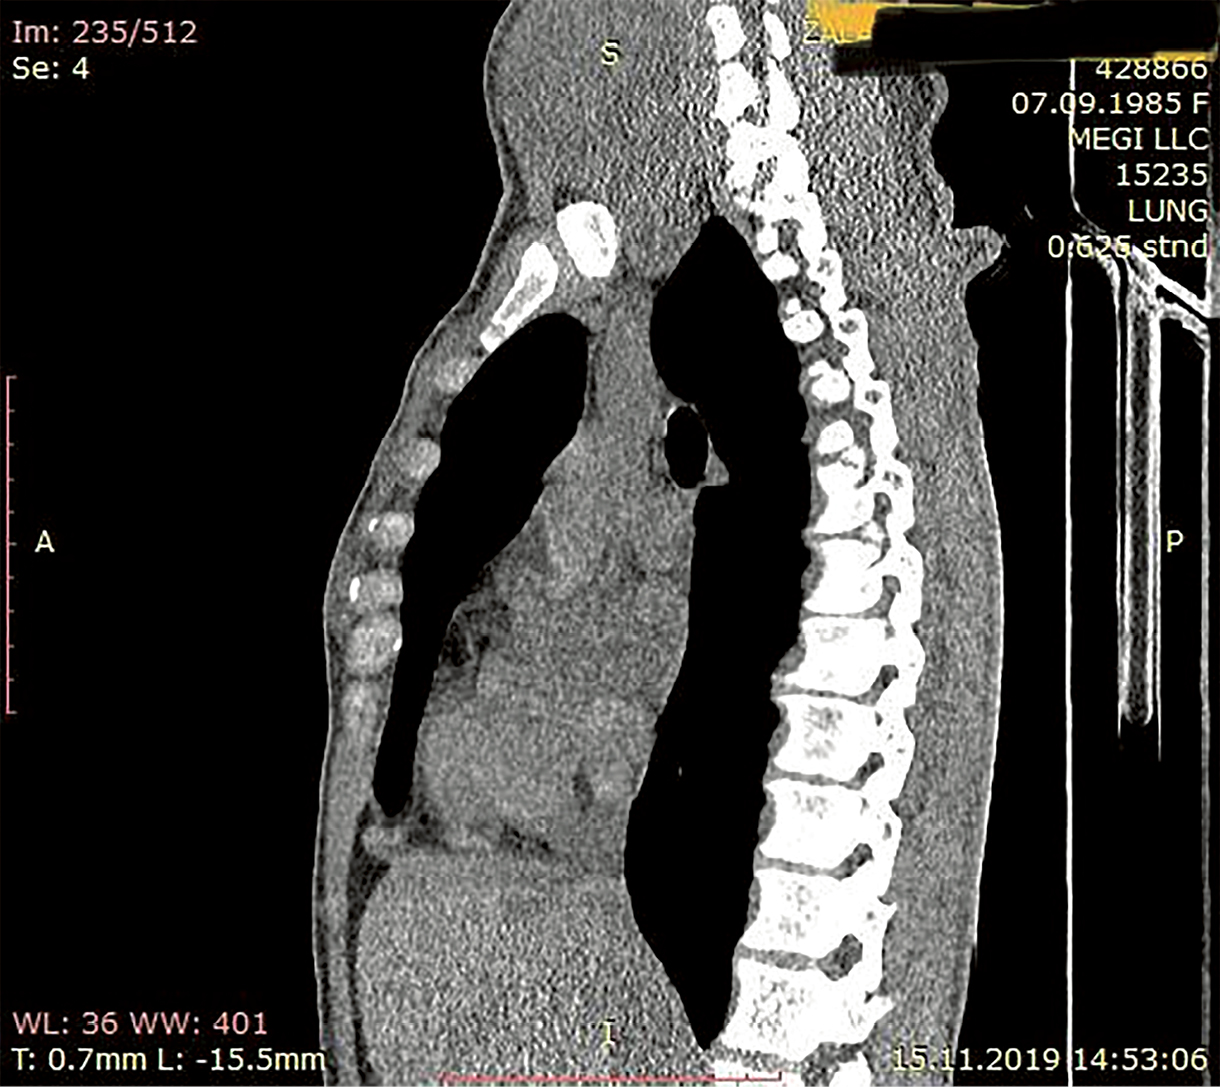

4. Рисунок 4. КТ органов шеи и средостения пациентки до лечения (боковая проекция). | |